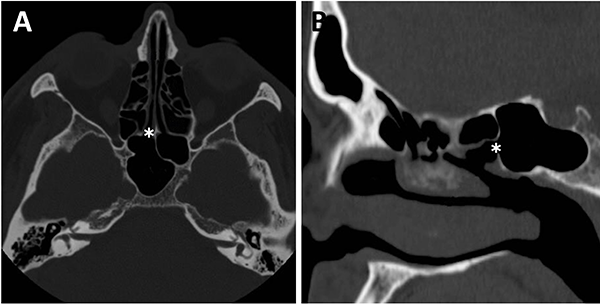

Al observar el seno esfenoidal debemos tener en cuenta la presencia de tabiques internos. Estos no deben ser tomados como referencia de línea media por su variabilidad. En este sentido, un dato cardinal es que un 90% los mismos se dirigen a las carótidas (fig. 13).1,15,23

La distancia intercarotidea determina el campo quirúrgico; a menor distancia es menor el campo y mayor el riesgo de lesión iatrogénica vascular. Otro punto a tener en cuenta es la presencia o no de cobertura ósea de la misma. En algunas oportunidades se va a encontrar recubierta por una lámina de hueso y, en otras, desprovista de la misma (fig. 13).15,23

Figura 13: Relación carótida – septaciones esfenoidales en TC cortes axiales. A) Septum interesfenoidal se inserta sobre meso carotídeo izquierdo (flecha blanca); B) Septaciones incompletas que se insertan sobre meso carotídeo en ambos senos esfenoidales (flechas blancas).

Figura 14: Localización de nervio óptico en TC cortes coronales. A) Nervio óptico dehiscente; B) Nervio óptico en su meso, con variante hiperneumatizada esfenoidal.